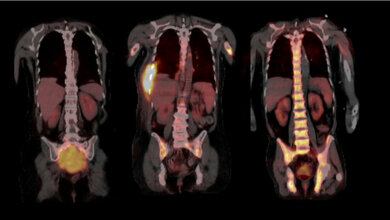

Doch auch bei der Diagnostik geht es mit Riesenschritten voran. Neben den neuen Möglichkeiten in der Bildgebung ist hier beispielsweise Liquid Biopsy ein Schlagwort. Die Nukleinsäureanalytik zum Nachweis von Tumorzellen und Tumor-DNA sorgt für Furore.